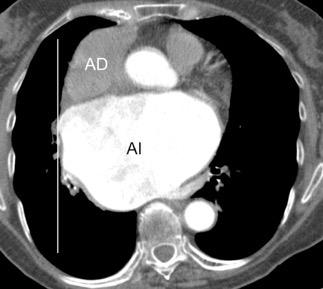

53. BPI .COMPRESIÓN Y DESPLAZAMIENTO HACIA ARRIBA DEL